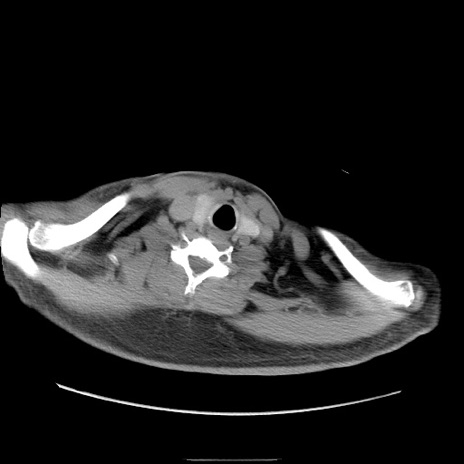

症例22(横断像)

【症例】50歳代男性

【主訴】腹痛

【現病歴】AVMからの被殻出血のため回復期リハ病棟入院中。 本日午後3時頃急に下腹部痛が出現した。

【既往歴】AVM、被殻出血、虫垂炎、高血圧

【身体所見】意識晴明、左半身不全麻痺、会話の理解は良好、36.5°C、腹部:膨隆、全体に板状硬、下腹部正中に圧痛点あり、反跳痛-、筋性防御不明、右下腹部にope scar

【データ】WBC 9400、CRP 0.06